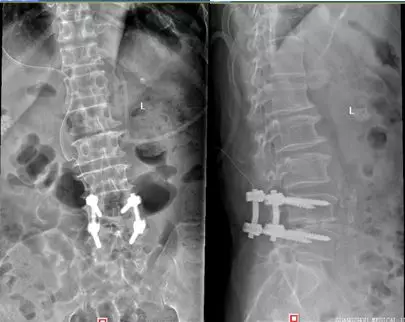

按照传统的手术方案,该患者需要分别进行L4/5减压融合和L3/4双侧锁孔减压摘除髓核手术,这样手术复杂、时间较长、存在诸多并发症的风险。经过详细的会诊和讨论后,吕浩然主任决定为其实施一站式杂交脊柱微创手术。

术中,先于腰4、5双侧置入椎弓根螺钉,椎间盘切除、行腰5神经根管扩大减压术。 然后置入椎间融合器、安放钛棒,最后腰3/4椎间盘髓核摘除、神经减压。

钉棒固定节段是通道系统下完成了融合,出血少。

临近的上一个椎间盘,显微镜下摘除,没有融合固定。

保留了一个节段,增加了腰椎活动度,节省了费用。